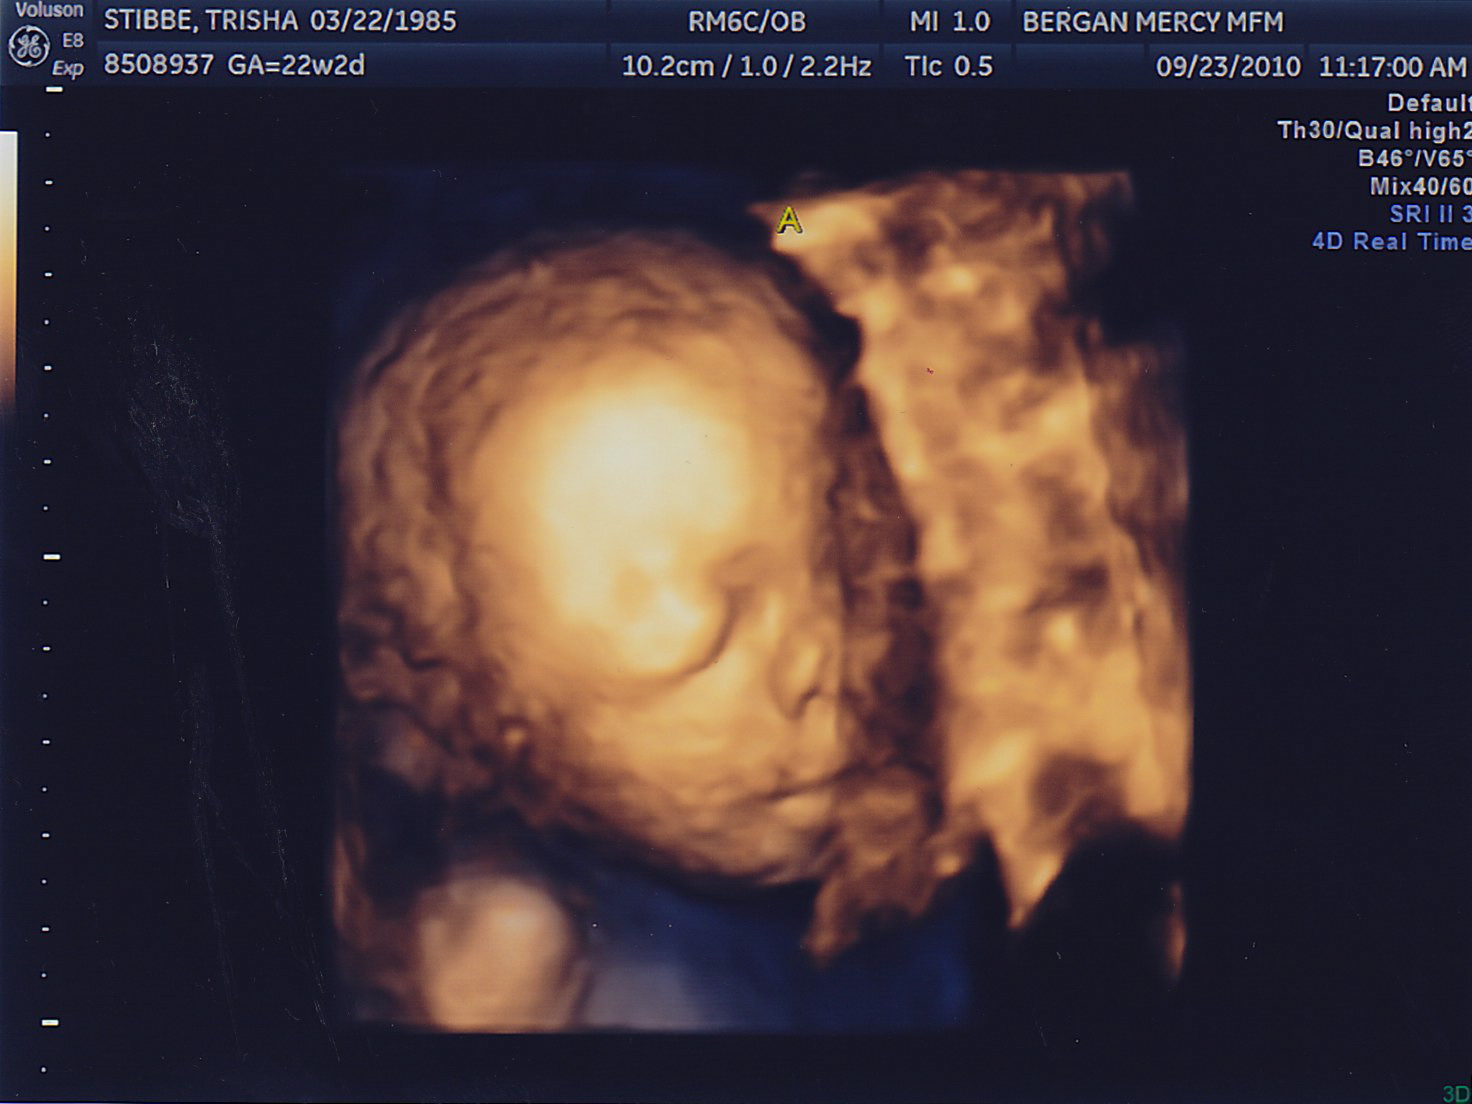

My sonographer Briana surprised me with 4D pictures! She was only able to get a good image of Baby A because Baby B is facing my back. One funny thing–for a while now they have both been on my right side and I could swear I looked lopsided. Then it started to kind of even out a little, and its because Baby A moved to the left! They’re finally learning to share 🙂 Last week they were both head down, and this week they’re both head up. Squirmy little guys.

Here are the little guys most recent pictures!

Hi Trish and Adam. Great pictures, I love the 4D’s. It’s amazing! It looks like Baby A is smiling in the one picture. He must be thinking about his Grandma. 🙂 Little B was being camera shy though. Little bugger.